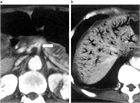

1. SMA閉塞症の疫学と初期診断:発症頻度は毎年5.6~8.6人/10万人と低いが、死亡率は24~94%と予後不良で、生命予後の改善には早期診断・治療が求められる(推奨度1J)

1. SMA閉塞症の画像診断による確定診断:問診・理学的所見・血液検査は必須であるが確定診断に至ることは困難であり、確定診断には画像評価が必須である(推奨度1J)